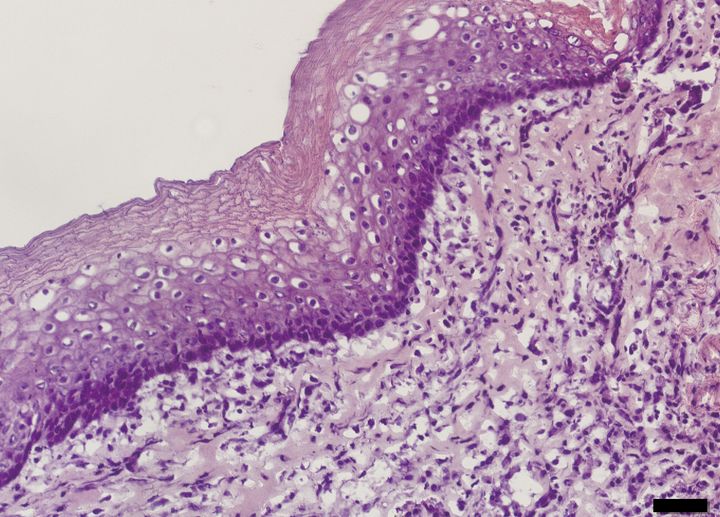

Tissue engineering has been used to construct natural oesophagi, which in combination with bone marrow stem cells have been safely and effectively transplanted in rats. The study, published in Nature Communications, shows that the transplanted organs remain patent and display regeneration of nerves, muscles, epithelial cells and blood vessels.

In this new study, the researchers created the bioengineered organs by using oesophagi from rats and removing all the cells. With the cells gone, a scaffold remains in which the structure as well as mechanical and chemical properties of the organ are preserved. The produced scaffolds were then reseeded with cells from the bone marrow. The adhering cells have low immunogenicity which minimizes the risk of immune reaction and graft rejection and also eliminates the need for immunosuppressive drugs. The cells adhered to the biological scaffold and started to show organ-specific characteristics within three weeks.

The cultured tissues were used to replace segments of the oesophagus in rats. All rats survived and after two weeks the researchers found indications of the major components in the regenerated graft: epithelium, muscle cells, blood vessels and nerves.